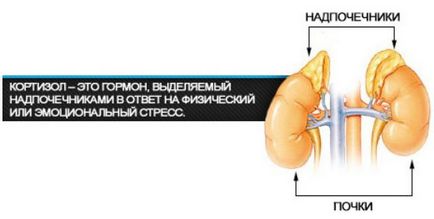

Hormon - egy biológiailag aktív szerves vegyület, amely felszabadul a belső elválasztású mirigyek, az belép a vért, és szabályozza az anyagcserét és egyéb funkciók. A hormonok olyan közléséért tájékoztatás a változások a test egy adott szerv vagy sejt. Ha az agy úgy dönt, hogy a beavatkozás okozta a helyzet megkívánja, akkor küldött anyagok, például hormonok, követeket egy sejt vagy szerv, amely a cél. Például, ha van élet a veszély, hogy az ember, a mellékvese mirigyek kortizol stresszhormon, amely felelős a robbanás ereje és energiája a szervezetben, ami segíthet egy személy túlélésre, vagy egyszerűen csak mozgasd a tragédia.

Amikor a test időszakát éli, a stressz, a mellékvese kortizol szekre célzó gyors mozgósítása szervezetre. A fehérjék a test teszi kortizol a szükséges energiát a harci stressz. Ez a hormon vezet a gyors szövetek regenerálódását, javítja a memóriát, koncentrációt. De a test szükséges, hogy az anyag átalakulhat az energia, így vége után a fehérjék a tanfolyam izomszövet. Ha folyamatosan olyan állapotban a stressz, az idegrendszer van terhelve, és a stressz, és ennek megfelelően osztják a kortizol stresszhormon, a szervezet elkezd fájni.